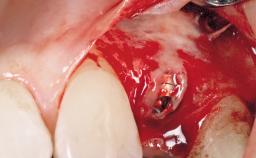

Late Placement of an Implant in a Maxillary Left Central Incisor Site

Bone Augmentation Horizontal|Staged

Augmentation Materials Xenogenous|Membrane

Soft Tissue Grafting Simultaneous